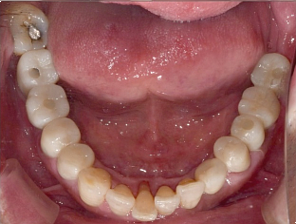

68세 남성

(전) 2021-11-05, (후) 2022-08-26

임플란트/크라운 시술 후

음식 섭취뿐만 아니라, 심미적인 개선으로

삶의 질이 높아진 환자분의 사례

치과에서 어떤 치료와 관리를 받는지에 따라 남은 삶의 질이 크게 달라질 수 있음을 절실히 느끼며